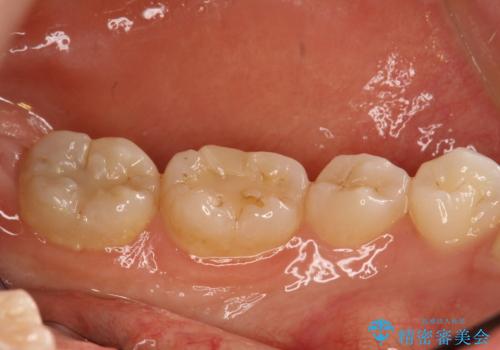

半年ぶりのPMTC

- 半年ぶりの来院で、クリーニング希望とのことでした。PMTC30分コースを行いました。

虫歯や歯周病を予防するには、歯垢をしっかり落とすことが大切です。

特に奥歯周辺はハブラシが入りにくく磨き残しの多いところです。毎回の磨き残しを放置せず、定期的に機械的なクリーニングを行うことが大切です。